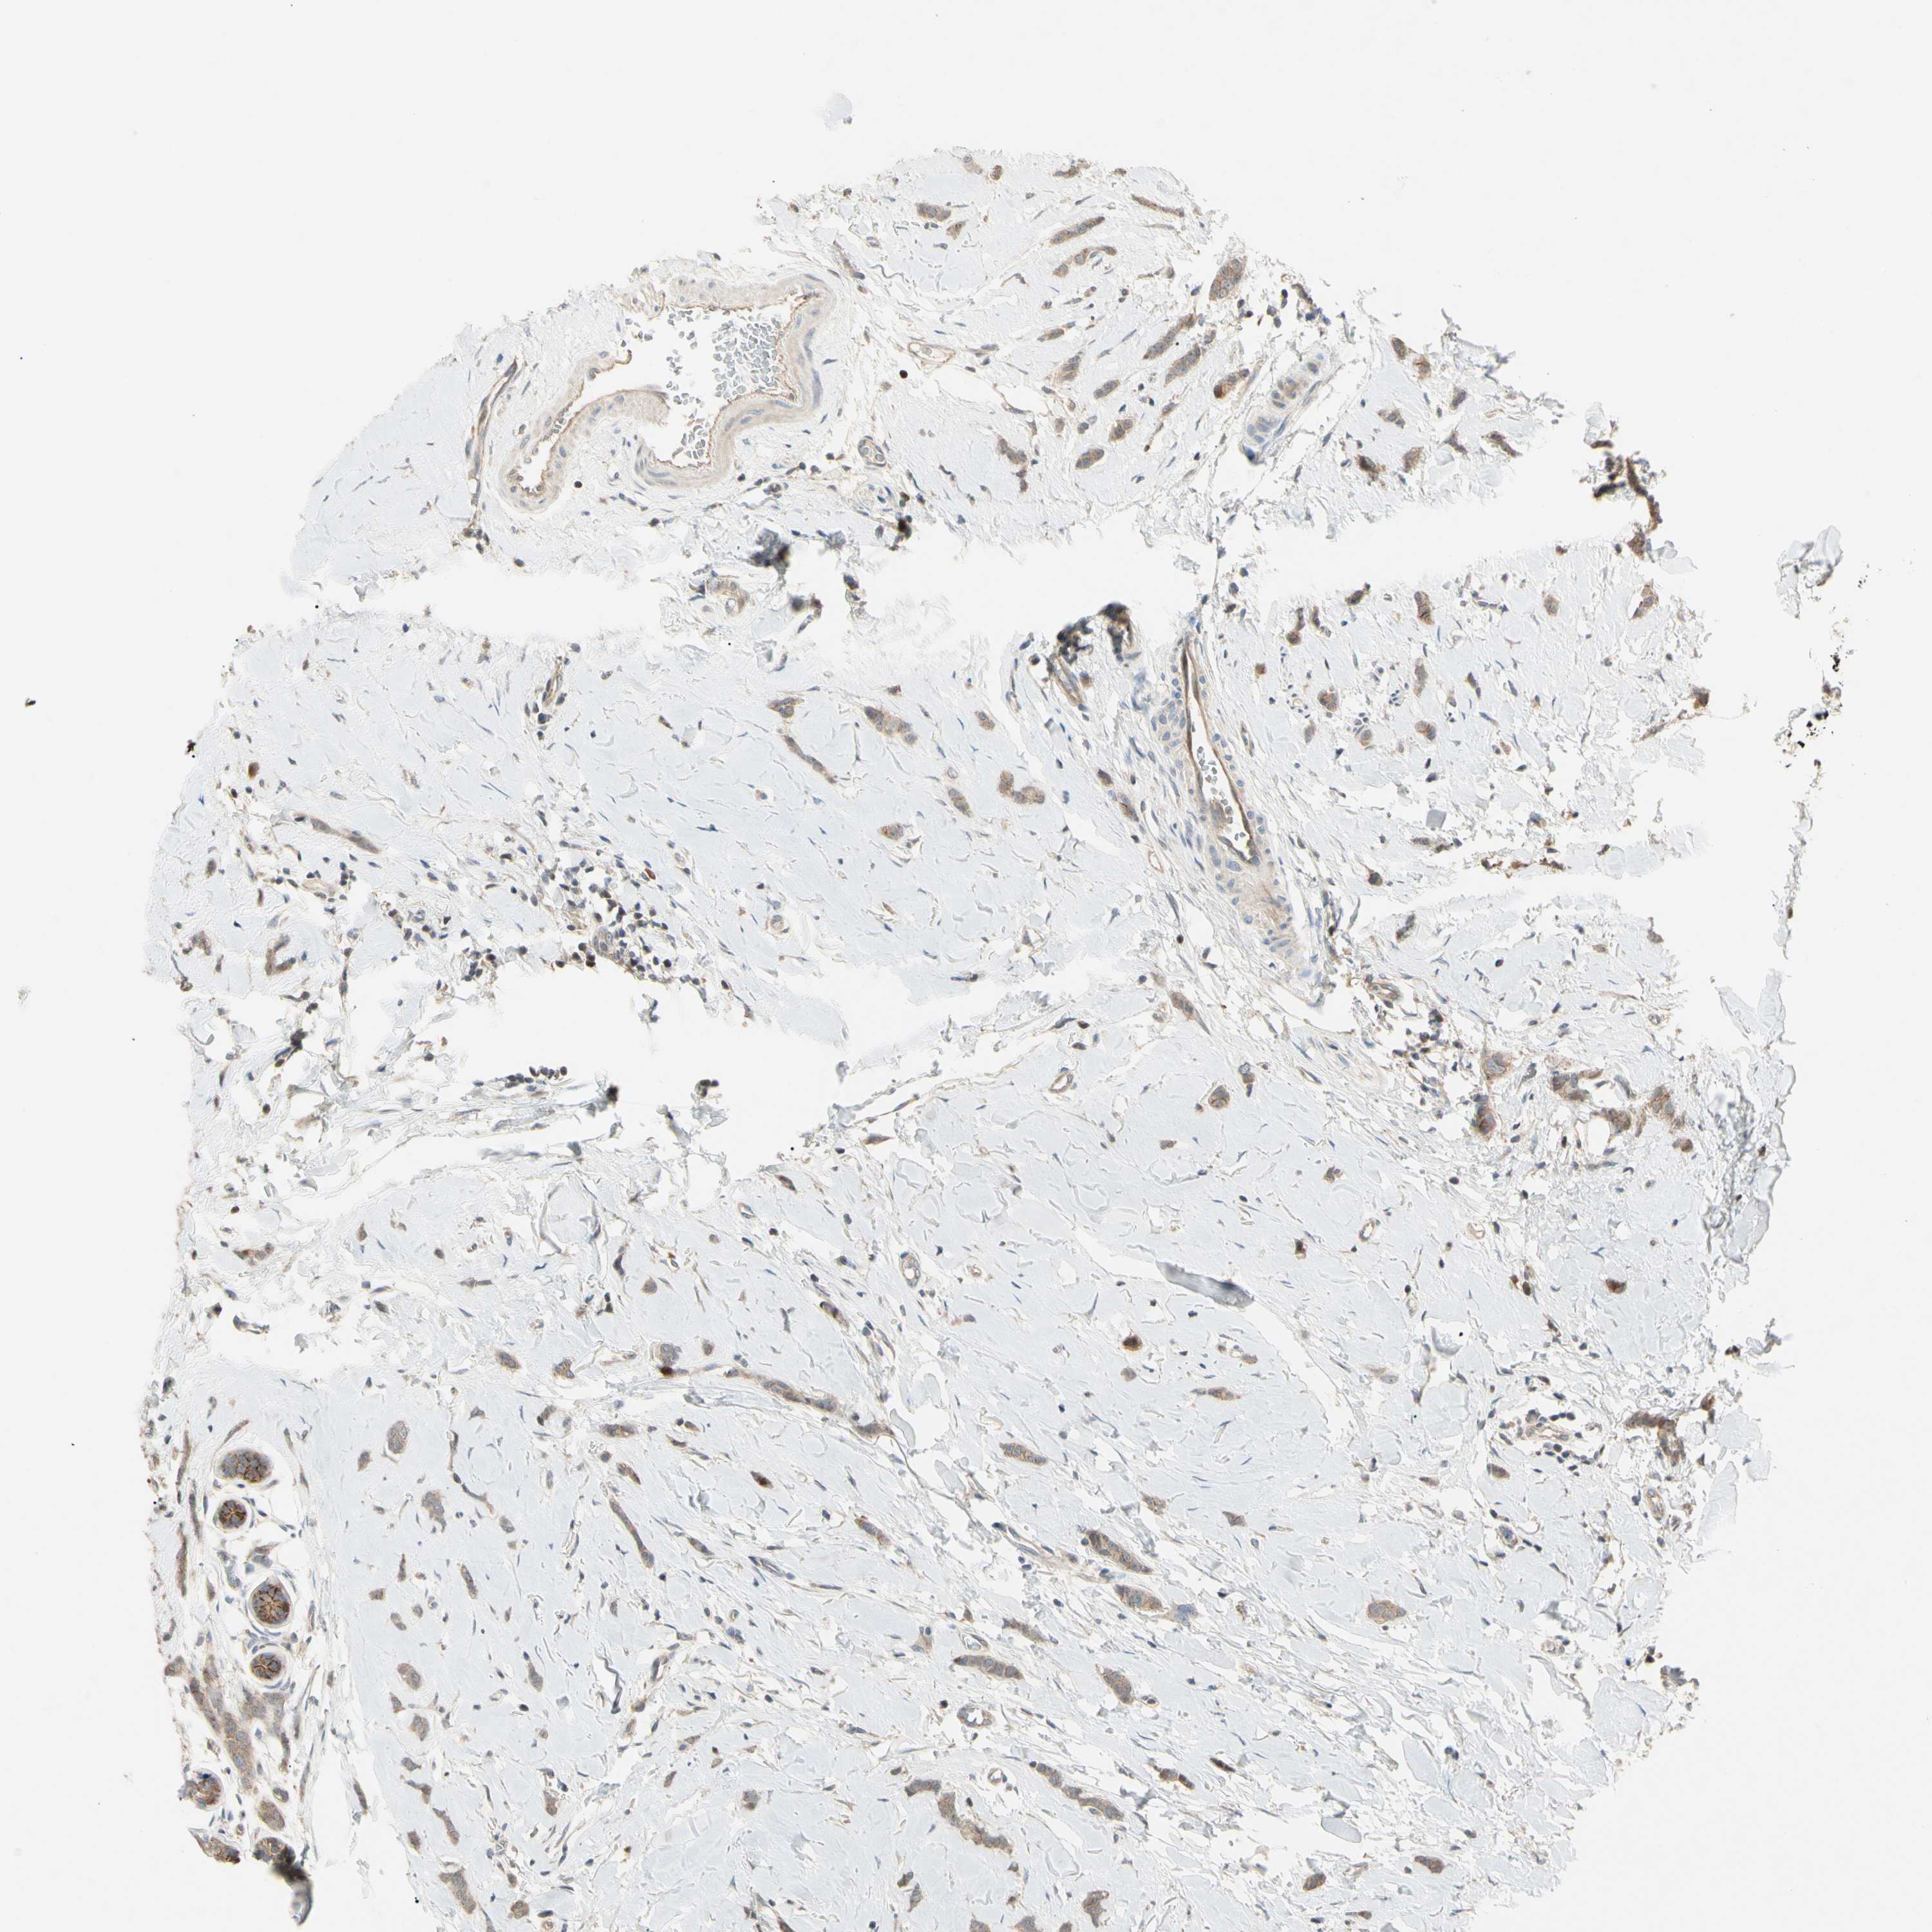

CANCER BREAST CANCER Show tissue menu

BRCA TCGA BRCA VALIDATION PROTEIN EXPRESSION